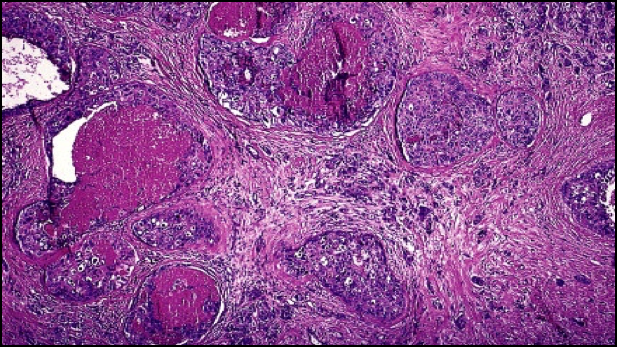

Carcinoma ductal invasor:Cuando la reducción de cadherinas y la degradación de la membrana basal permite el paso de las células tumorales al tejido conjuntivo subyacente invadiendolo y sustituyéndolo (desmoplasia) en la que hay una sustitución de la grasa mamaria normal por una masa de celular de consistencia dura.Al microscopio observamos áreas de hemorragia y otras de necrosis.